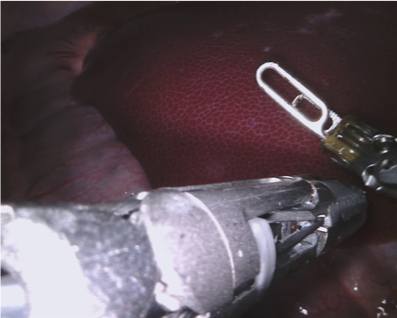

Our challenge was made up of 3 sub-problems. The first was binary instrument segmentation, where each frame was separated into da Vinci Xi instruments and a background class, which contained an ultrasound probe, surgical clips and porcine tissues. The second task was instrument part segmentation, where we scored the participants on whether they could correctly segment each articulating part of the instrument (see Fig. 3). Our final task was to segment and classify the instruments (see Fig. 4).

We provided the first 225 frames of 8 sequences as training data and kept the last 75 frames of those 8 sequences as test data. 2 of the full 300 frame sequences were kept as test sequences. Test labels were kept hidden from the participants. Our datasets contain 7 different robotic surgical instruments. The Large Needle Driver, Prograsp Forceps, Monopolar Curved Scissors, Cadiere Forceps, Bipolar Forceps, Vessel Sealer and additionally a drop-in ultrasound probe, which is typically held in the jaws of the Prograsp Forceps instrument. Samples from the training datasets are depicted in Fig. 2 and examples of the different instrument types are shown in Figure 3 and 4.

IV-D Type Segmentation

The final challenge was to identify each instrument type from the list of Large Needle Driver, Prograsp Forceps, Monopolar Curved Scissors, Vessel Sealer, Fenestrated Bipolar Forceps and Grasping Retractor (see Fig. 4). Only 6 teams participated in this challenge, due particularly to the significant increase in difficulty in recognizing many of the da Vinci instruments from one another.